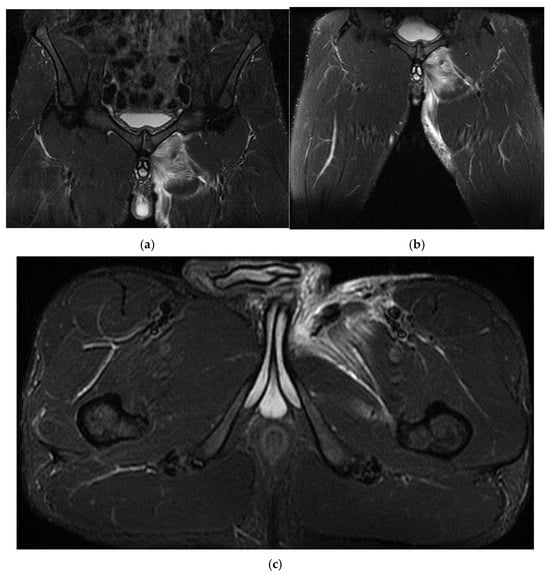

3.1. Case 1: Vastus Lateralis Tear with Prepatellar Hematoma

Right back, 22 years old, national-team player from a rural area, professional first-league athlete, 198 cm, 110 kg. In the initial case, the right back sustained injuries to the knee and the distal portion of the left thigh during a training session, attributed to a lateral concussion and the “opening” of the internal compartment. The clinical examination revealed pain, swelling, edema, a bubble knee, relative functional impairment, and restricted active and passive movement of the left knee. A sprain of the left knee was suspected, with potential damage to the meniscus, cruciate ligaments, and collateral ligaments. Although the MRI did not indicate any damage to the intra-articular structures, it did reveal a substantial prepatellar extraarticular hematoma, resulting from a muscle tear in the vastus lateralis muscle, along with significant edema of the soft tissue. The extraarticular edema is evident in the non-homogeneous Ts and STIR hyperintense, accompanied by T1 hypo- and hyperintense. Post-traumatic edema of the adjacent soft tissue is depicted in STIR as an altered diffused hyperintense (Figure 1, Figure 2 and Figure 3).

The spinal MRI revealed no evidence of degenerative lumbar disc pathology or radiculopathy (Figure 5). Magnetic resonance imaging (MRI) and radiographic examination of the pelvis revealed an old avulsion injury with a detached bone fragment at the insertion site on the left ischial tuberosity, involving the semitendinosus, semimembranosus, and biceps femoris muscles (collectively referred to as the ischium-calf muscles). This condition has led to the development of pseudoarthrosis and bone edema at the level of the ischial tuberosity. The sciatic nerve is positioned tangentially to the inflammatory response. Despite the detachment, the bone fragment remains vascularized due to the maintained insertion of the ischial calf muscles, preventing it from becoming a bone splinter (Figure 6 and Figure 7).

(a) Pelvic MRI: coronal stir acquisition, (b) pelvic MRI: sagittal PD fat sat acquisition, (c) pelvic MRI: sagittal PD fat sat acquisition, (d) axial stir acquisition, (e) axial stir acquisition, (f) axial T1 acquisition.

In the third case, a left winger reported experiencing sharp pain in the inner left thigh, which severely impaired both active and passive movements during sprints. The left winger, aged 32, has 14 years of experience as a first-league professional in Romania and is a national team member from an urban area, standing 189 cm tall and weighing 90 kg. MRI confirmed the diagnosis of tears and disinsertion of the short adductor tendon and I- and II-degree tears of the obturator externus, pectineus, and adductor longus muscles. STIR sequences show the disinsertion of the short adductor tendon with a gap between the tendon and pubis, with the presence of significant hyperintense alterations, which were also present in the obturator externus, pectineus, and adductor brevis muscles, representing various degrees of fiber tears associated with blood clots (Figure 8).

(a) Thigh MRI: coronal stir acquisition, (b) thigh MRI: coronal stir acquisition, (c) thigh MRI: axial stir acquisition.